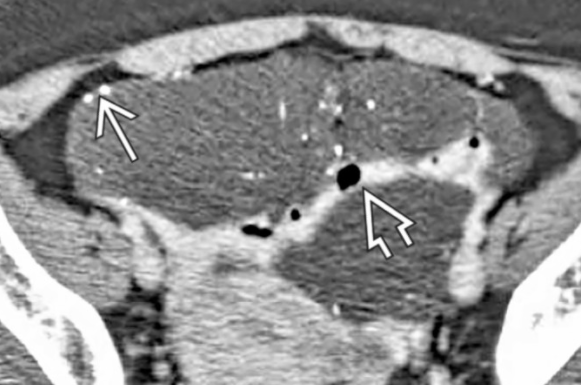

- Kystique (0 HU) ou chyleux (-20 HU)

- Multiloculés

- Pas de prise de contraste

- Pasd d’effet de masse (entoure les vaisseaux)

Lymphangiome Retropéritonéal